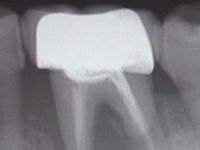

早龋,一次消毒即可进行补牙,中龋或深龋,则需m三至五次,如果涉及到牙神经则需根管治疗。